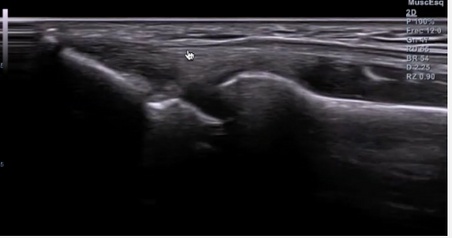

Ultrasound support for better clinical decisions

We use musculoskeletal ultrasound as a complementary tool when it adds value to your assessment and treatment plan.

It helps us visualise tendons, muscles and soft tissue structures, support clinical hypotheses and monitor how certain injuries evolve over time.

We are always transparent: we are not radiologists. Ultrasound is not used for medical diagnosis but as an additional layer of information to personalise and guide your rehabilitation.